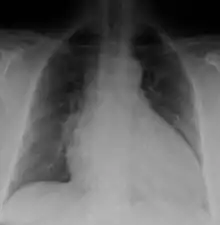

Generalized enlargement of the heart is seen upon normal chest X-ray. Pleural effusion may also be noticed, which is due to pulmonary venous hypertension.[27]

The electrocardiogram often shows sinus tachycardia or atrial fibrillation, ventricular arrhythmias, left atrial enlargement, and sometimes intraventricular conduction defects and low voltage. When left bundle-branch block (LBBB) is accompanied by right axis deviation (RAD), the rare combination is considered to be highly suggestive of dilated or congestive cardiomyopathy.[28][29] Echocardiogram shows left ventricular dilatation with normal or thinned walls and reduced ejection fraction. Cardiac catheterization and coronary angiography are often performed to exclude ischemic heart disease.[27]